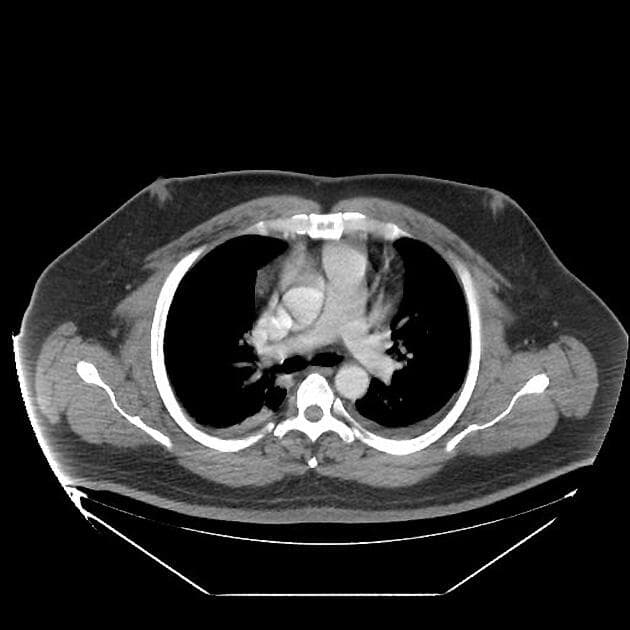

- Các nhánh đường mật trong gan (intrahepatic biliary radicles) giãn nhẹ.

- Ống mật chủ (common bile duct) giãn, thấy nhiều viên sỏi nhỏ có tín hiệu thấp ở đoạn cuối.

- Túi mật (gallbladder) căng giãn, chứa nhiều viên sỏi nhỏ.

- Tụy (pancreas) to lan tỏa và phù nề, xung quanh có dịch quanh tụy lan dọc theo các khe mỡ vùng sau phúc mạc, rõ hơn ở phía bên trái.

- Ống tụy (pancreatic duct) có vị trí, chiều dài và đường kính bình thường, cấu trúc bên trong đồng nhất, bờ trơn đều.

Sỏi túi mật (cholelithiasis) và sỏi ống mật chủ (choledocholithiasis) là những nguyên nhân phổ biến gây viêm tụy cấp (acute pancreatitis). Trong trường hợp này, viêm tụy cấp được phát hiện trên hình ảnh cộng hưởng từ đường mật tụy (MRCP) được thực hiện do có triệu chứng vàng da tắc mật và đau vùng thượng vị.

Viêm tụy cấp là một tình trạng lâm sàng phổ biến, thường do sỏi mật gây ra, đặc biệt khi chúng làm tắc ống mật chủ tại nhú tá lớn (ampulla of Vater). Trường hợp này cho thấy các hình ảnh điển hình trên MRCP bao gồm to toàn bộ tụy, dịch quanh tụy và dấu hiệu tắc nghẽn đường mật do sỏi ống mật chủ. Sự hiện diện của nhiều viên sỏi nhỏ ở đoạn cuối ống mật chủ xác nhận nguyên nhân bệnh. Chẩn đoán sớm bằng MRCP cho phép xử trí kịp thời, bao gồm nội soi mật tụy ngược dòng (ERCP) để lấy sỏi. Việc phân biệt viêm tụy cấp với các nguyên nhân khác gây đau bụng và vàng da như viêm đường mật hay ung thư tụy là rất quan trọng vì các bệnh này đòi hỏi can thiệp khác nhau.